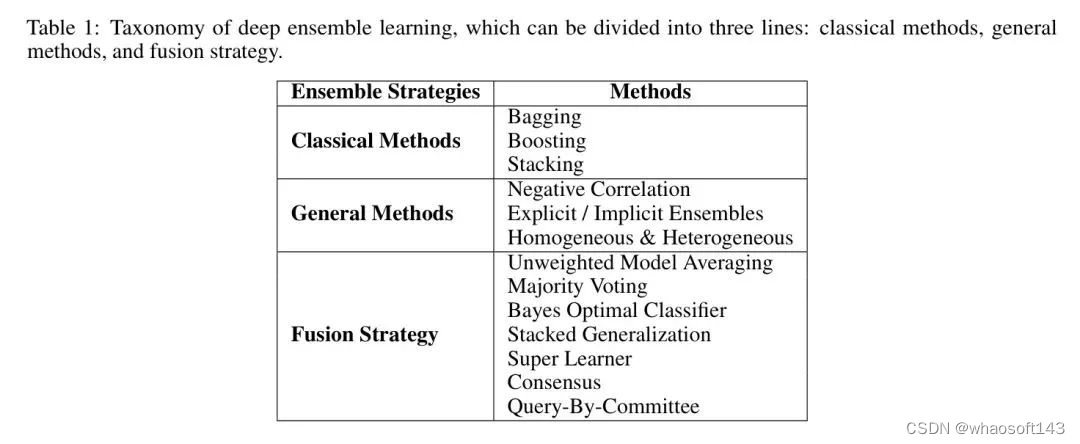

探索数据集可以对模型输入有一个概述,这涉及到观察图像的代表样本并分析元数据,例如细胞类型和异常的分布。为了说明类别的分布,作者在图 3 中绘制了一个直方图。在图中,显然 'RBC' 类占最大比例,数量约为 2500,其次是 'WBC' 类和 'Platelets' 类。

ADA-YOLO 模型针对医学影像中的多目标检测,解决了物体遮挡或截断等在医学影像中常见的挑战性问题。如图 4 所示,提出的检测方法可以成功检测到任何大小的红细胞缺失,与基准相比是一个很大的改进。ADA-YOLO 在所有类别中具有 0.918 的召回率,优于基准。